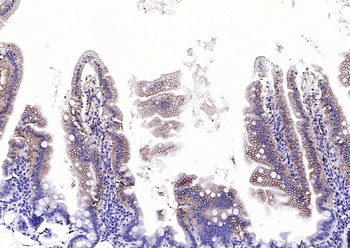

IHC-P image of human endometrial cancer tissue using anti-Emp1 (2.5 ug/ml)

Immunohistochemical staining of human endometrial cancer tissue using anti-Emp1 (2.5 ug/ml)